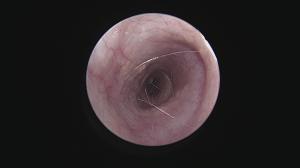

繰り返す外耳炎で意外と知られていない原因に「ゴミの蓄積」があります。

ゴミと言っても成分は細菌、脂、汗、毛、炎症細胞・・などなどが混じって形成されています。

そのゴミが鼓膜付近に蓄積していると、点耳薬や洗浄(一般的は)は効果を十分に発揮できません。

まずはこの汚れをしっかり除去することが重要ですね。

この除去はやはり大変です・・鼓膜があるのと、耳の道が狭いこと(晴れている場合も多い)、動くのでそもそも無理・・

道内では珍しい耳道内視鏡治療を積極的に行っています(麻酔下で初めに除去することでその後のケアが楽になるので他施設で行っていない施術を当院では取り入れています)

これがなかなか技術が必要ですが、処置後の経過が良いことがモチベーションになります!

この耳道内視鏡はあまり知られていませんが、お困りの症状にあった処置ができますので今後もアナウンスしていきます!